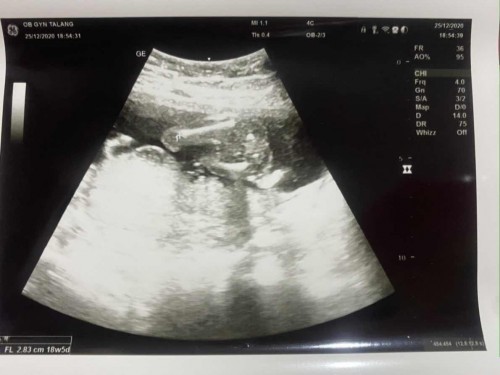

ตอนนี้น้อง 18 week แล้วนะคะ น้องแข็งแรง สมบูรณ์ทุกอย่าง #แต่กังวลเรื่องน้ำหนักของลูกค่ะ #พอมีคำแนะนำมั้ยค่ะ

พักผ่อนไห้เพียงพอ ทานอาหารที่มีเเคลเซี่ยมกับโปรตีนเยอะๆค่ะ